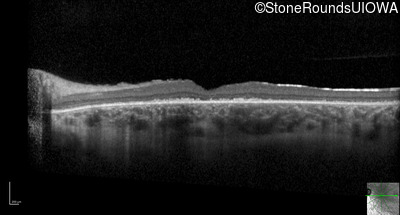

Optical Coherence Tomography - Right - 20/200 +2

Exemplar / OCT Stack

OCT Stack